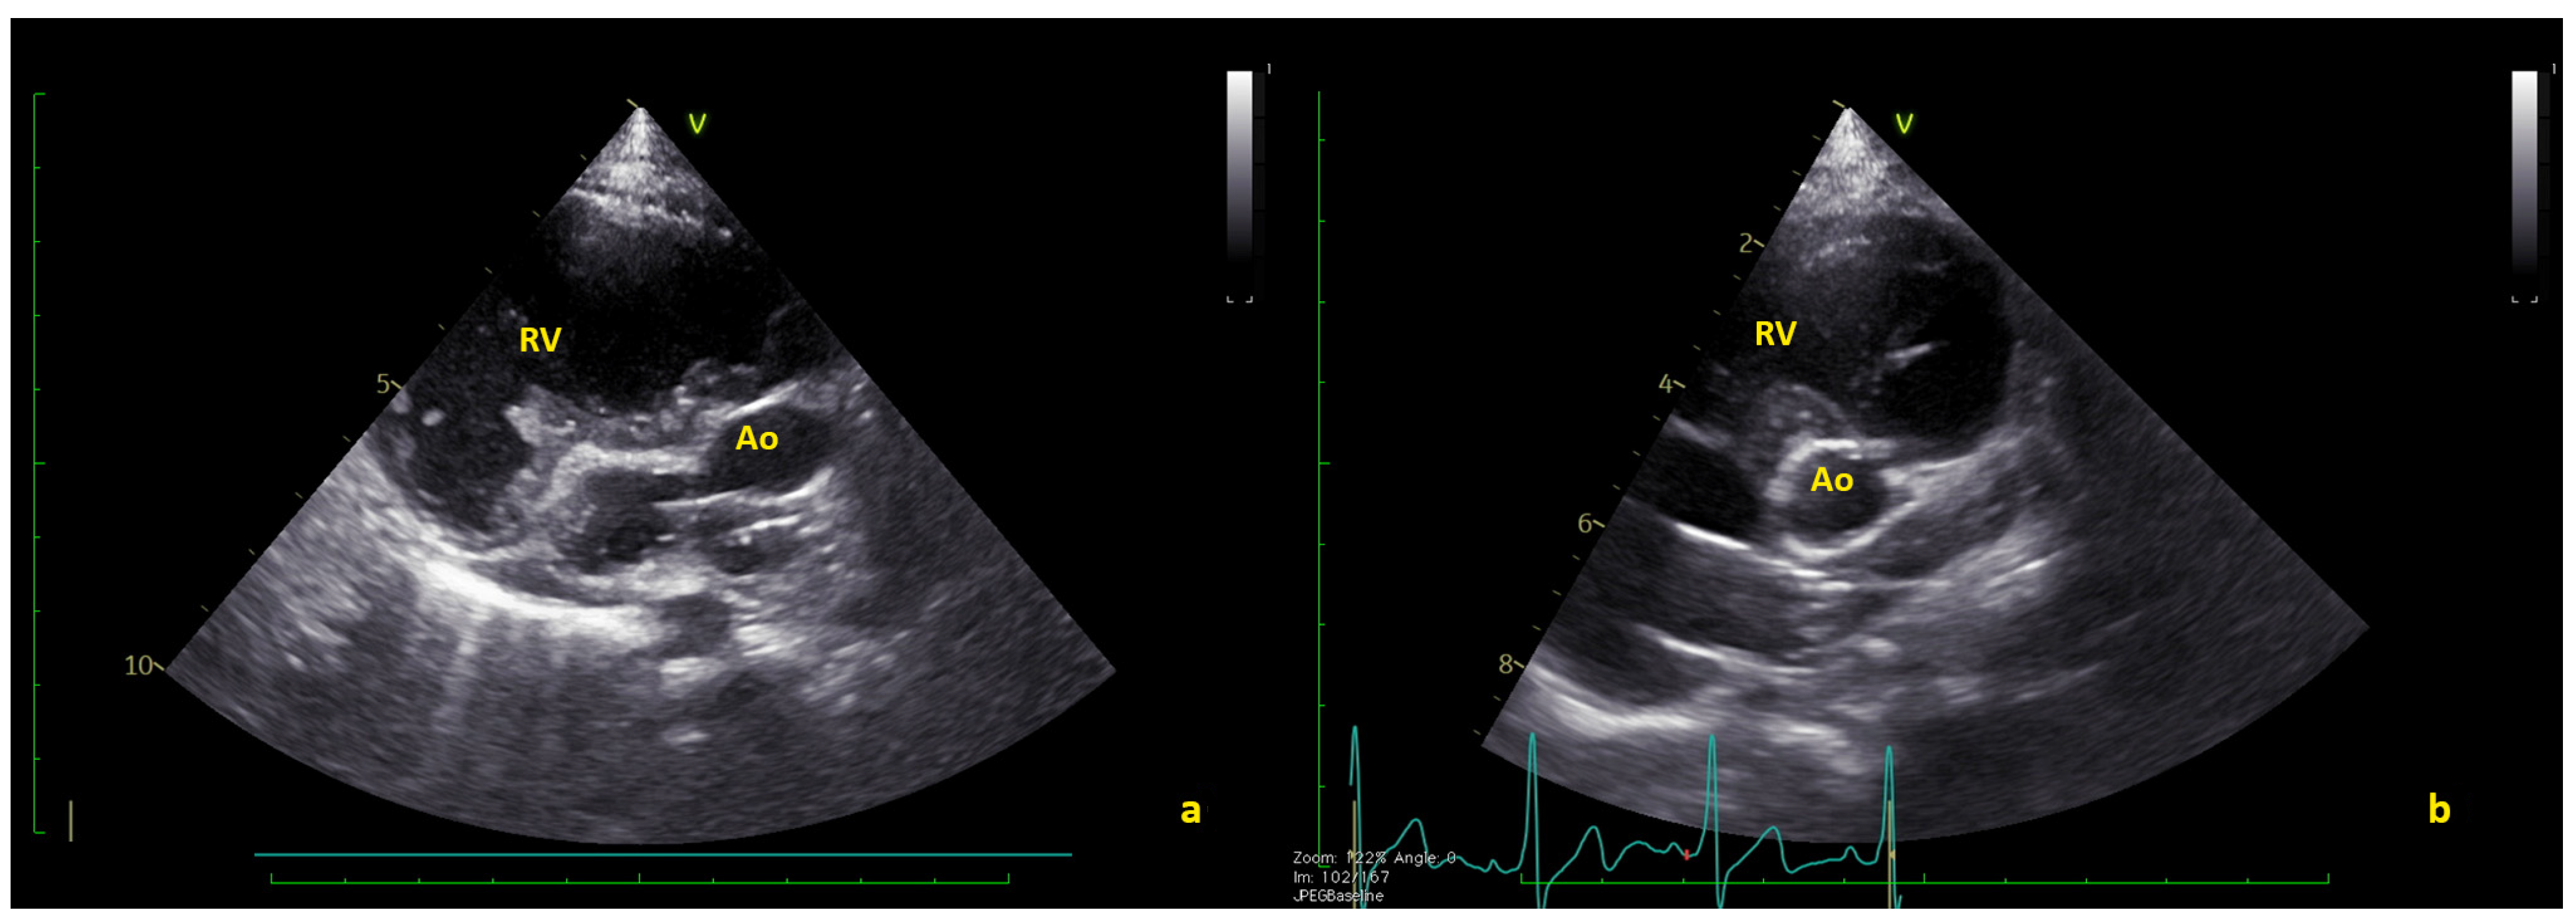

2. Experience